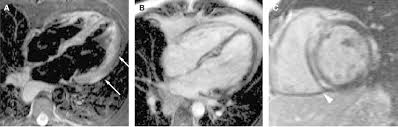

The Radiology Assistant Ischemic And Non Ischemic Cardiomyopathy

The Radiology Assistant Ischemic And Non Ischemic Cardiomyopathy from radiologyassistant.nl

More specifically, it is described as. Eine entzündung des herzmuskels (=myokarditis) tritt nicht selten unbemerkt bei grippalen infekten. Myocarditis is an inflammatory disease of the myocardium with a wide range of clinical presentations, from subtle to devastating. Mrt in der diagnose und monitoring neurodegenerativer erkrankungen. Myocarditis cardiosclerosis is a pathology in which parts of the myocardium involved in inflammation die and are replaced by connective tissue. Classified as idiopathic, these cases are attributed to genetic factors, viral myocarditis, and autoimmune mechanisms. Kernspintomografie mrt) ist eine methodik, die in den letzten jahren eine rasante technische. Journal of the american college of cardiology vol.

Ein in der mrt nachweisbares lge ist dabei nachweislich mit einer ungünstigeren prognose und einer erhöhten rate kardialer ereignisse assoziiert.